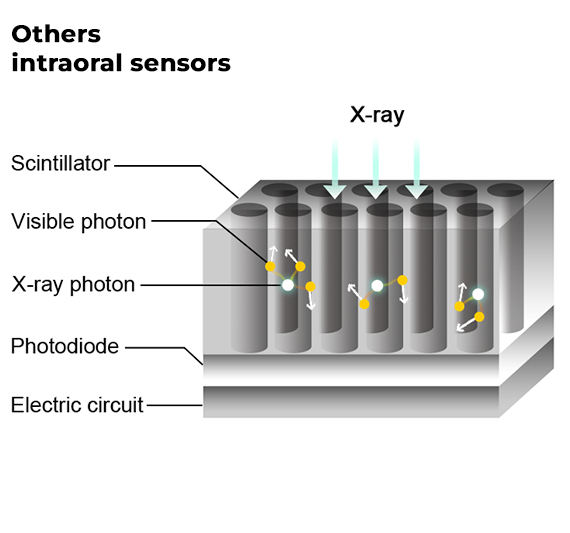

Il sensore intraorale Tecnoray RVG19X introduce in odontoiatria la più recente tecnologia photon-counting, una soluzione avanzata già utilizzata nella diagnostica TC di ultima generazione.

Grazie all’imaging diretto, evita la dispersione luminosa tipica dei sistemi indiretti, garantendo immagini cliniche stabili, nitide e ad altissima qualità.

Il sensore intraorale Tecnoray RVG19X utilizza chip al silicio di ultima generazione, una tecnologia avanzata che sostituisce il tradizionale ioduro di cesio (CsI).

Grazie a questa innovazione, il sensore offre immagini nitide e prive di sfocature, garantendo una diagnosi più precisa e un’esperienza di lavoro più efficiente.